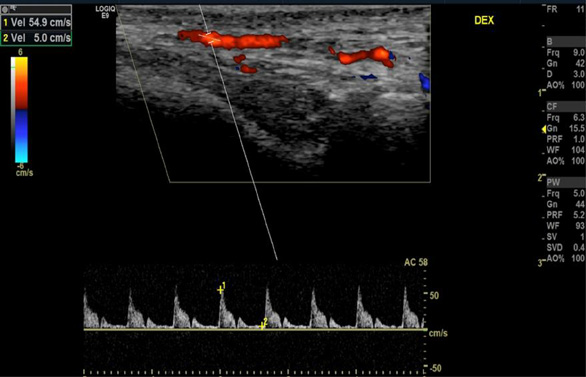

Five years later, at the follow-up visit, the patient did not feel any pain or discomfort in the temporal area bilaterally. No inflammatory signs of temporal arteries were detected (Fig. 3). The control color-coded duplex sonography showed no halo sign, and normal blood flow velocities were registered (Fig. 4). It was concluded that there were no clinical or ultrasound signs of temporal vasculitis.

Fig. 4. Color-coded duplex sonography of superficial temporal artery after the treatment (2024)

Normal blood flow velocities of the right (A) and left (B) superficial temporal arteries were observed without the ‘halo’ sign.